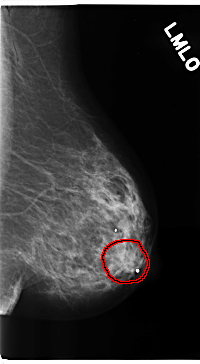

C_0206_1.LEFT_MLO

FILE: C_0206_1.LEFT_MLO.OVERLAY

TOTAL_ABNORMALITIES 1

ABNORMALITY 1

LESION_TYPE MASS SHAPE LOBULATED MARGINS ILL_DEFINED

ASSESSMENT 4

SUBTLETY 3

PATHOLOGY MALIGNANT

TOTAL_OUTLINES 1

BOUNDARY